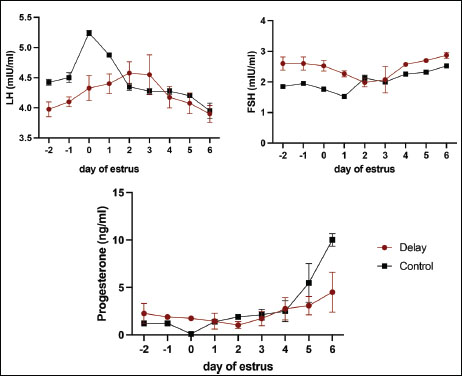

Hormonal analysis revealed that DO cows exhibited significantly lower LH levels during the pre-onset estrus phase compared with NO cows (4.13 ± 0.20 vs. 4.73 ± 0.39 mIU/ml, p < 0.05) (Table 2). This finding supports the role of elevated SBP in suppressing LH pulsatility and delaying the LH surge critical for ovulation. In contrast, FSH levels were higher in DO cows during pre-estrus (2.58 ± 0.19 vs. 1.85 ± 0.09 mIU/ml, p < 0.05), indicating that progesterone does not directly inhibit FSH secretion. Instead, the elevated FSH likely reflects a compensatory response to reduced negative feedback from estradiol due to smaller dominant follicles in DO cows. LH concentrations did not differ significantly between groups, while progesterone remained elevated longer in DO cows, consistent with delayed luteolysis and follicular dynamics.

Correlation analysis further demonstrated a strong negative relationship between LH and FSH levels during pre-onset estrus (r=−0.694, p=0.00), underscoring the differential regulation of these gonadotropins during DOO (Table 3). Progesterone was negatively correlated with FSH pre-estrus (r=−0.436, p=0.022), suggesting complex feedback interactions modulating FSH levels indirectly through estrogen rather than direct progesterone inhibition. These hormonal patterns align with ultrasound observations of smaller dominant follicles and larger retained corpora lutea in DO cows during pre-estrus, supporting the endocrine environment characterized by suprabasal progesterone suppressing LH release timing and amplitude, while FSH rises as a compensatory mechanism to altered estrogen feedback.

Fig. 3. Hormonal profiles in cows with ovulation delay (DO) compared with normal ovulating cows (NO) measured before estrus, at the onset of estrus, and throughout the luteal phase. This figure depicts the temporal changes in key reproductive hormones, such as progesterone and estradiol, highlighting the distinctive hormonal dynamics associated with the timing of ovulation. Differences between the DO and NO groups indicate altered endocrine regulation in delayed ovulation, which may explain the observed variations in ovarian function and follicular development across the estrous cycle stages.

In this study, the reduced and prolonged LH pulse in cows with delayed ovulation was comparable to previous findings in high-productivity cows with delayed ovulation. This hormonal pattern showed that the pre-ovulatory LH amplitude remained the same for many days following the expression of estrus. Three days later, the cows were spiked with a much lower average LH pulse than that of the normal cows. Delay ovulation causes cows to release less estrogen because of fewer follicles before estrous expression. Initiating an LH surge at the right time and increasing levels becomes difficult. Multiple studies have demonstrated that insufficient energy intake can be attributed to the inability or delay of LH surge. Hypothalamic Insulin growth factor-1 (IGF-1) receptor insensitivity also stops ovulation by inhibiting LH surge (Endo, 2022). IGF-binding proteins (IGFBP-2, IGFBP-3, and IGFBP-5) in the pituitary gland fluctuate with cow diet and affect LH secretion. Further studies are required to confirm this association. LH and FSH levels were negatively correlated (p−0.694) throughout the follicular phase. Higher FSH levels were expected in ovulation-delayed cows before estrus to counteract the negative feedback of the hypothalamus by estrogen from the dominant follicle. Small follicles in cows with delayed ovulation indicate that estrogen does not trigger a feedback loop. Follicle development continues past estrus due to the inability of the ovary to generate negative feedback (Borş and Borş, 2020). This was observed in elevated FSH levels near estrus, similar to the results of this study (Fig. 2).

Progesterone levels derived from the CL are integral to the regulation of the hypothalamus-pituitary-gonadal axis (Abreu et al., 2018). A significant portion of the effects of progesterone is mediated through endometrial histotroph secretions, which impact embryonic and fetal growth and developmental biology, or through gonadotropin secretion, which affects follicular function and oocyte competence (Borş and Borş, 2020). Furthermore, endometrial histotroph secretion may modify estrous patterns in animals. During delayed ovulation, progesterone hormones increase throughout the follicular phase, delaying ovulation, aging the oocyte, and affecting fertilization (Di Nisio et al., 2022).

After ovulation, the follicle anatomically becomes the CL to increase the progesterone levels during gestation and implantation. However, in delayed ovulation, cows increase progesterone (suprabasal progesterone) from proestrus to estrus and inhibit the pituitary gland, which in turn suppresses FSH and LH production, resulting in smaller follicles during proestrus. Smaller follicles, which extend the estrous phase, reduce the capability of hypothalamic LH receptors. Subsequently, this inhibition leads to a decreased release of the LH surge, ultimately causing a delayed ovulation (Duncan, 2021). This study supports all the aforementioned assertions. Previous studies have shown that cows with irregular ovulation have significantly higher suprabasal progesterone levels than normal cows during the follicular phase. Intriguingly, this study revealed that cows with delayed ovulation symptoms were still capable of undergoing ovulation, albeit with delay. According to previous research, almost 70% of repeat breeders in livestock have suprabasal progesterone levels > 1 ng/ml during the onset of estrus (Prashar et al., 2023). When the suprabasal levels of progesterone increase, follicular receptors respond by reducing GnRH secretion, which subsequently leads to decreased follicle proliferation. The dominant follicles expanded to 3.2 cm after estrus expression on day 0 in DO cows (Fig. 1). The results of Prashar et al. (2023) are consistent with the findings of this study. Progesterone alters the pulsative action of LH and slows ovulation (Santos et al., 2016). In the presence of progesterone, there were fewer receptor activities in the pituitary gland than in the hypothalamus. This suggests that the hormone directly inhibits or slows down LH pulsation. Progesterone also influences the release of hypothalamic kisspeptin upstream. The oocyte quality decreases when suprabasal progesterone levels are high. This causes them to age, proteins to become phosphorylated, and meiosis to begin again from the diplotene stage of prophase I (Santos et al., 2016). In contrast to the NO cows, the DO cows exhibited a low LH pattern and sustained mature oocytes for a longer duration than the normal cows. Oocytes of cows with delayed ovulation may be of inferior quality due to their age, thereby increasing the risk of fertilization failure. Oocytes from cows with delayed ovulation require further investigation both in vivo (AI) and in vitro In vitro fertilization (IVF).